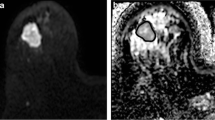

Comparisons between fractional enhancement and predicted enhancement maps in three representative patients are illustrated in Fig. 3. Both highlight similar regions of enhancing and non-enhancing tissues.

Examples of single axial slices from three representative Wilms tumours. a, c, e Fractional enhancement maps of the Wilms tumours (outlined in red), measured using gadolinium. b, d, f The same slices of the same Wilms tumours from predicted enhancement maps, predicted using Eq. 3 (without gadolinium). Increased signal represents greater enhancement, and hence more viable tissue. Tumour details: A and B—subtype, mixed; age at scan, 11 years. C and D—subtype, blastemal; age at scan, 1.8 years. E and F—subtype, mixed; age at scan, 1.08 years